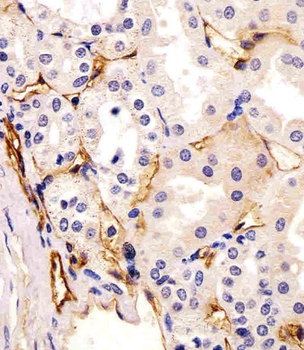

IHC staining of FFPE human pancreatic carcinoma with CD73 antibody (clone NT5E/2545). HIER: boil tissue sections in pH9 10mM Tris with 1mM EDTA for 10-20 min and allow to cool before testing.